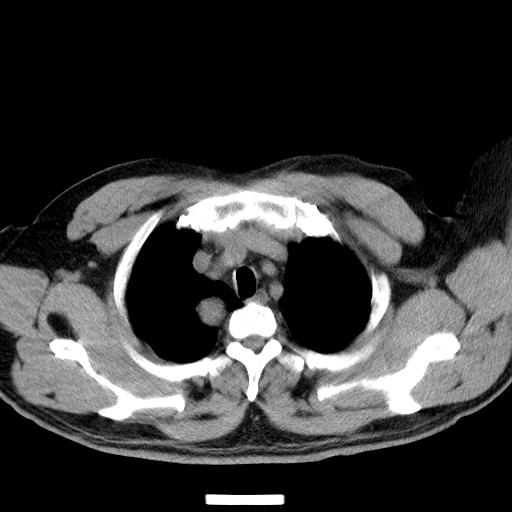

男,51岁,体检时发现右上纵隔高密度影。

右上纵隔脊柱旁圆形结节,密度均匀,边界清楚——考虑神经源性肿瘤!